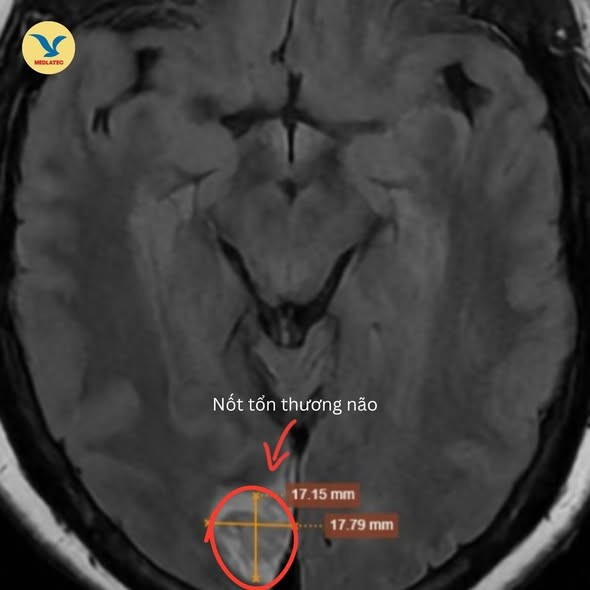

3 tuần sau, bà H. đến Phòng khám Đa khoa Medlatec Tây Hồ để thăm khám. Kết quả xét nghiệm thấy chỉ số mỡ máu tăng cao. Hình ảnh chụp MRI sọ não phát hiện nốt tổn thương vùng chẩm bên phải nghĩ tới tổn thương huyết khối mạn tính hội lưu tĩnh mạch lan vào nhánh nhỏ tĩnh mạch vỏ não lân cận.

Hình ảnh MRI phát hiện tổn thương vùng chẩm - Ảnh BVCC

Bác sĩ chẩn đoán xác định bệnh nhân có nhồi máu vùng chẩm mạn tính do huyết khối hội lưu tĩnh mạch, đây là nguyên nhân gây ra biểu hiện suy giảm thị lực bên phải của bà H.